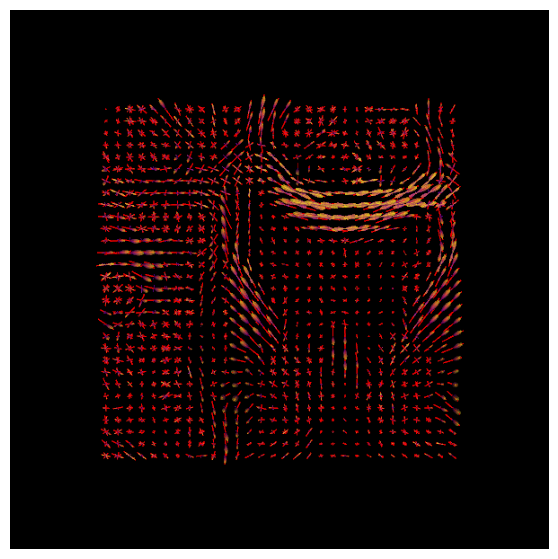

We will now use the basis functions generated above to create Fiber Orientation Densities, or FODs. These are estimates of the amount of diffusion in each of three orthogonal directions. As described in the introductory chapter, these are analogous to the tensors that are used in traditional diffusion studies. However, MRtrix allows for the estimation of multiple crossing fibers within a single voxel, and can resolve the diffusion signal into multiple directions.

To do this, we will use the command dwi2fod

to apply the basis functions to the diffusion data. The “-mask” option specifies which voxels we will use; this is simply to restrict our analysis to brain voxels and reduce the computing time. The “.mif” files specified after each basis function will output an FOD image for that tissue type:

In order to view these FODs, we will combine them into a single image. The command mrconvert

will extract the first image from the wmfod.mif file, which is the image with a b-value of 0. The output of this command is then used as the input into an mrcat

command which combines the FOD images from all three tissue types into a single image that we will call “vf.mif”:

The white matter FODs can then be overlaid on this image, so that we can observe whether the white matter FODs do indeed fall within the white matter, and also whether they are along the orientations that we would expect. The command for mrview is:

mrview vf.mif -odf.load_sh wmfod.mif